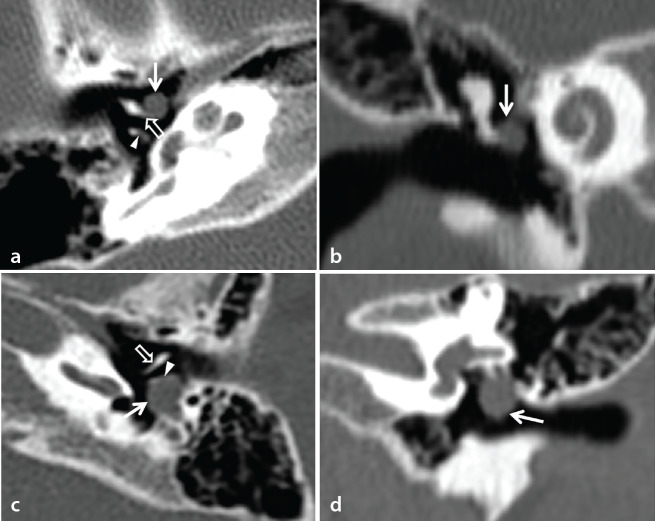

Results: Of the 81 CCs, surgery revealed 43 CCCs and 38 OCCs. On CT scans, CCC was frequently seen as a small (median: 3.15 mm), round to oval (65.1%) mass, most commonly located in the anterosuperior quadrant (74.4%) of the middle ear with less frequent ossicular erosion (14.0%). In contrast, OCC was frequently seen as a large (median: 6.70 mm), irregular (94.7%) mass, most commonly located in the posterosuperior quadrant (68.4%) of the middle ear with frequent ossicular erosion (55.3%). The size, shape, location, and presence of ossicular erosion were significantly different between the two types. Overall, the CT and surgical stages of CCs demonstrated good agreement (kappa value: 0.77) and the CT and surgical stages of OCCs were statistically significantly higher than those of CCCs (P < 0.001 in both).

Abstract Image